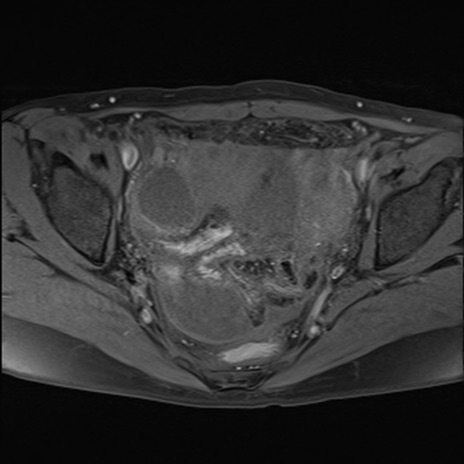

症例39 脂肪抑制T1WI(横断像)

MRI(4日後)